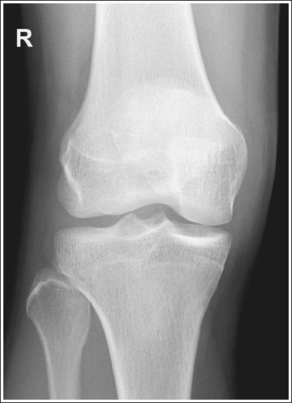

The knee demonstrates an AP projection. The medial and lateral femoral epicondyles are in profile, the femoral condyles are symmetrical, the intercondylar eminence is centered within the intercondylar fossa, and the tibia is superimposed over 0.25 inch (0.6 cm) of the fibular head.

The knee joint space is open, the anterior and posterior condylar margins of the tibia are superimposed, the intercondylar eminence and tubercles are demonstrated in profile, and the fibular head is demonstrated approximately 0.5 inch (1.25 cm) distal to the tibial plateau.

• The anterior and posterior condylar margins of the tibia are superimposed if the correct central ray angulation, as determined by the patient's upper thigh and buttocks thickness, is used. By studying the tibial plateau region, you will see that the tibial plateau slopes distally approximately 5 degrees from the anterior condylar margin to the posterior condylar margin on both the medial and lateral aspects (Figure 6-72). Only if the central ray is aligned parallel with the tibial plateau slope is an open knee joint space obtained.

• Determining the central ray angulation. When a patient is placed in a supine position, the degree and direction of the central ray angulation required depend on the thickness of the patient's upper thigh and buttocks. This thickness determines how the lower leg and the tibial plateau align with the IR. Figure 6-73 shows a guideline that can be used to determine the central ray angulation for different body sizes; it illustrates the relationship of the tibial plateau to the imaging table as the patient's upper thigh thickness increases. Note that a decrease occurs in femoral decline, and a shift occurs in the direction of the tibial plateau slope as the thickness of the thigh decreases. Because of this plateau shift, the central ray angulation must also be adjusted to keep it parallel with the plateau and to achieve an open knee joint. For optimal AP knee projections, measure from the patient's anterior superior iliac spine (ASIS) to the imaging table on either side to determine the central ray angulation to use for each knee examination. When measuring this distance, do not include the patient's abdominal tissue. Keep the calipers situated laterally next to the ASIS. If the measurement is less than 18 cm, a 5-degree caudal angle should be used. If the measurement is 19 to 24 cm, a perpendicular beam should be used. If the measurement is greater than 24 cm, a 5-degree cephalad angle should be used. Using the correct central ray angulation not only results in an open knee joint space but also provides optimal demonstration of the intercondylar eminence and tubercles without foreshortening.

• Analysis of joint space narrowing. On an AP knee projection with adequate positioning, joint space narrowing is evaluated by measuring the medial and lateral aspects of the knee joint, which are also referred to as compartments. The measurement of each of these compartments is obtained by determining the distance between the most distal femoral condylar surface and the posterior condylar margin of the tibia on each side. Comparison of these measurements with each other, with measurements from previous images, or with measurements of the other knee determines joint space narrowing or a valgus or varus deformity. In a valgus deformity the lateral compartment is narrower than the medial compartment; in a varus deformity the medial compartment is narrower (see Images 56 and 57). Precise measurements of the compartments are necessary to ensure early detection of joint space narrowing and are best obtained when the knee joint space is completely open. If an inaccurate central ray angulation was used for an AP knee projection, the knee joint is narrowed or obscured, the intercondylar eminence and tubercles are foreshortened, and the tibial plateau is demonstrated.